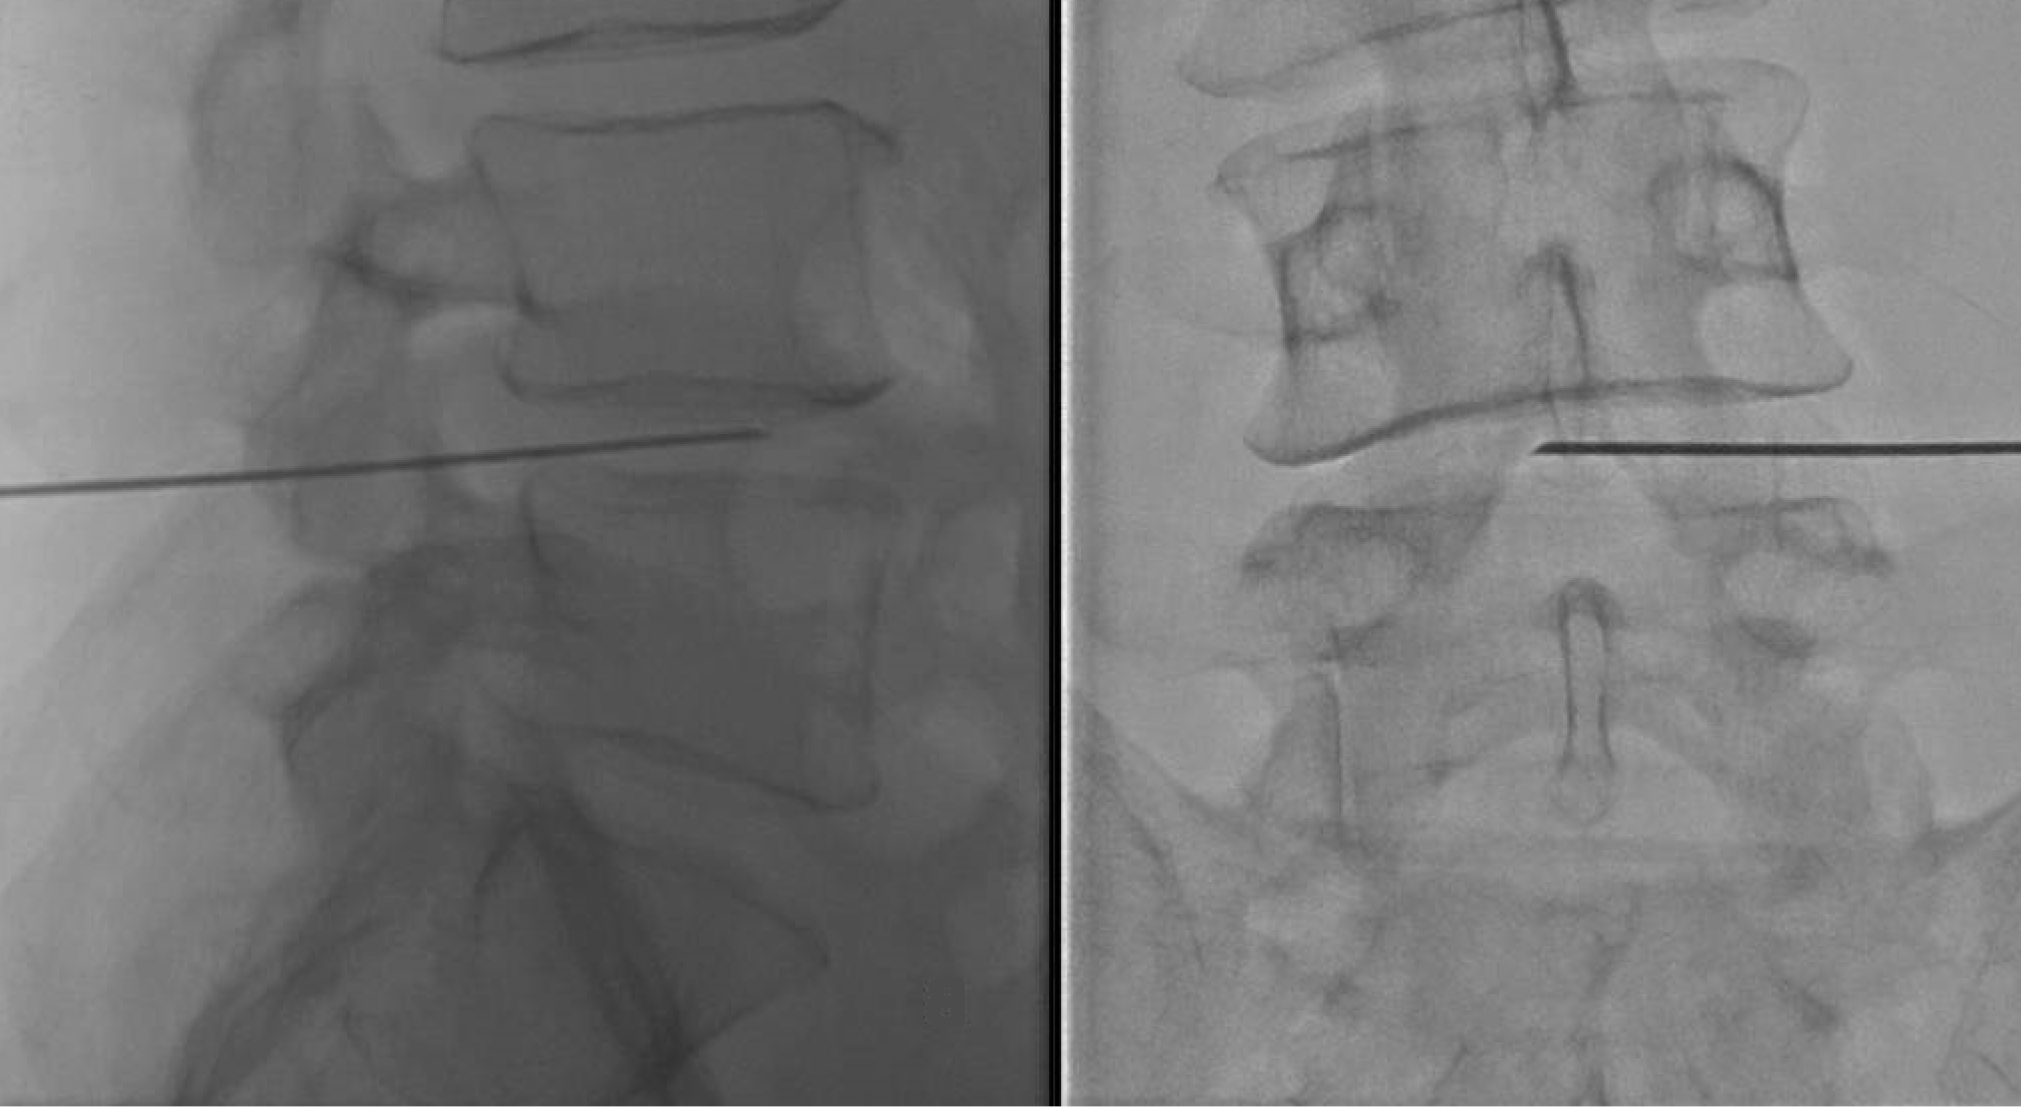

2. Infiltración Epidural (Interlaminar o Transforaminal)

- El ozono se administra cerca de la raíz nerviosa afectada, bajo guía fluoroscópica o ecográfica.

- Técnica más efectiva para hernias con compresión radicular severa.

- Inyección intradiscal: Se aplica una mezcla de oxígeno-ozono directamente en el núcleo pulposo del disco afectado, mediante control fluoroscópico o guiado por TAC. Esta es la técnica más efectiva y específica para reducir el volumen discal.

- Guía imagenológica (TAC o radioscopia) para punción precisa del disco.

Se aplica una mezcla de oxígeno-ozono directamente en el núcleo pulposo del disco intervertebral afectado. Se realiza bajo control radiológico estricto, ya sea mediante fluoroscopía o tomografía axial computarizada (TAC).